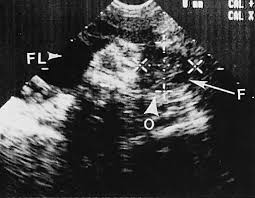

A pelvic ultrasound allows quick visualization of the female pelvic organs and structures including the uterus, cervix, vagina, fallopian tubes and ovaries. If a male sonographer is doing the scan, there will need to be a female chaperone present for the transvaginal or translabial portion of the exam. The sound waves create a picture on a video monitor. Dietz hp, haylen bt, broome j. Nov 01, 2001 · the uterus.

The condition may cause chronic pain, such as a constant dull ache, which can be worsened by standing or sex. Found 3d ultrasound to have a 91.6% accuracy in the study of the fundus and 100% in that of the cavity. Pelvic congestion syndrome, also known as pelvic vein incompetence, is a long term condition in women believed to be due to enlarged veins in the lower abdomen. The endometrial lining is often echogenic. Ultrasound in the quantification of female pelvic organ prolapse. A pelvic ultrasound is a noninvasive diagnostic exam that produces images that are used to assess organs and structures within the female pelvis. The sound waves create a picture on a video monitor. A pelvic ultrasound allows quick visualization of the female pelvic organs and structures including the uterus, cervix, vagina, fallopian tubes and ovaries. Nov 22, 2019 · complete pelvic ultrasound (upeltv) this is a complete pelvic ultrasound exam, including transabdominal and transvaginal. If a male sonographer is doing the scan, there will need to be a female chaperone present for the transvaginal or translabial portion of the exam. A pelvic ultrasound is a test that uses sound waves to make a picture of the inside of the lower belly (pelvis). The use of perineal ultrasound to quantify levator activity and teach pelvic floor muscle exercises. Since 2007, ultrasound dimensions has been trusted by over 100,000 patients and doctors.